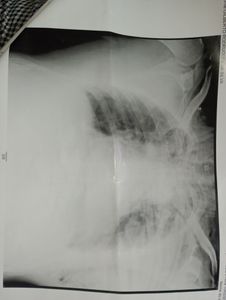

Geralmente para ganhar um pouco a mais faz algumas viagens, foi solicitada uma viagem para silveirânia à noite e logo na entrada da roça o assalto foi realizado pelos passageiros com a tentativa de homicídio. Foram três tiros na cabeça porém a arma mascou, ele aproveitou a situação e saiu correndo desnorteado no escuro e conseguiu chegar na estrada, onde atingiu a lateral da cabine de um caminhão ( o que acabou salvando a sua vida). O motorista do caminhão parou e prestou Socorro, assim como um colega taxista que por coincidência também passava pelo local, Gil continua internado desde o dia do acidente 08/02/2023.

Além dos pontos na cabeça devido a batida na carreta, o impacto fez com que a traquéia dele se compense indo ar subcutâneo para pescoço e peitoral. A perna direita esta imobilizada, e o braço esquerdo, sendo que estão acompanhando a evolução para cirurgia da clavícula, seus pulmões se expandiram devido a água que entrou. Seus dentes tbm foram afetados, deram "um jeito" aqui para amenizar a situação, pois sua boca esta bastante machucada por dentro. Mas posteriormente terá que ir ao dentista e fazer fisioterapia de reabilitação, além de acompanhamento psicológico, ele esta muito abalado.

O valor arrecadado será destinado para pagar sua reabilitação uma vez que Rio pomba não possui profissionais com as qualificações necessária para uma boa evolução e reabilitação para que possa voltar a dirigir quanto antes, sendo que optaram por não operar a luxação da clavícula que visivelmente está fora do lugar, fisioterapia para perna também, terapia a laser e medicações.